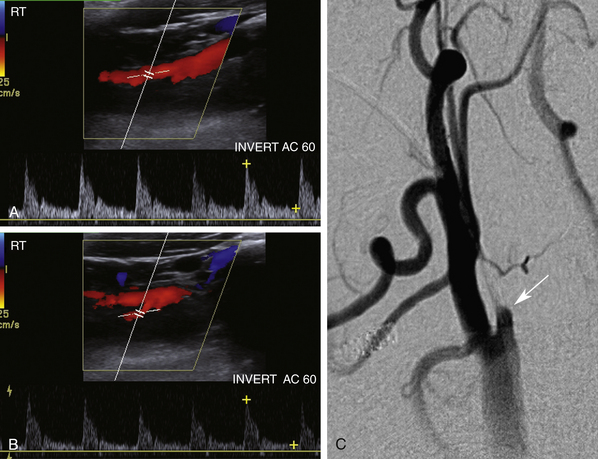

У этого 78-летнего мужчины возникла транзиторная ишемическая атака. Допплеровские сигналы для просмотра включают правую ОСА вблизи ее начала и двусторонние ВСА ( рис. 10-12 ). С какой стороны аномалия? Почему формы сигналов ненормальные? Для анализа также передается кривая правой позвоночной артерии. Как вы объединяете это исследование? Где должно быть поражение, чтобы все выводы имели смысл?

РИСУНОК 10-12. Случай 2. A. Доплеровский спектр правой общей сонной артерии (ОСА), полученный вблизи ее начала. B — Допплеровский спектр правой проксимальной внутренней сонной артерии (PICA). C, Допплеровский спектр правой позвоночной артерии (VERT). D: Допплеровский спектр левой проксимальной части внутренней сонной артерии (PICA). E. Магнитно-резонансная ангиография демонстрирует стеноз безымянной артерии ( стрелка ).

Анализ

Обратите внимание, что все доплеровские сигналы с правой стороны затухают и имеют меньшую скорость. Левая ВСА нормальна по внешнему виду и скорости. Появление пульсуса парвуса (плохая амплитуда) и тардуса (позднего подъема вверх) всегда указывает на то, что вы находитесь ниже стеноза. Поскольку результаты односторонние, они указывают на то, что стеноз имеется только справа. Форма волны позвоночной артерии двухфазная, что обычно указывает на поражение подключичной артерии. В этом случае, чтобы учесть все результаты, поражение должно находиться в проксимальном, невизуализируемом сегменте артериального дерева и должно затрагивать безымянную артерию, поскольку это единственный сосуд, который может вызвать нарушения кровотока как в сонной, так и в позвоночной артериях. справа.

Диагностика

Стеноз безымянной артерии высокой степени.

Что следует помнить

Может существовать важная артериальная патология, выходящая за пределы прямой визуализации сонной артерии (как проксимальной, так и дистальной). Такая патология выявляется только при допплерографии.

1. Всегда сравнивайте форму сигнала и результаты допплеровских измерений скорости на обеих сонных артериях. Различия могут быть не такими очевидными, как в этом случае, но даже незначительные различия следует рассматривать как подозрительные.

2. Стенозы возникают в аортальном отхождении брахиоцефальных артерий. Наиболее частыми локализациями являются безымянная, левая общая сонная и левая подключичная артерии.

3. Двухфазный кровоток в позвоночной артерии предполагает поражение подключичной артерии («подключичное обкрадывание»). Если нарушения кровотока включают ипсилатеральные правые сонные артерии, думайте о безымянном поражении.